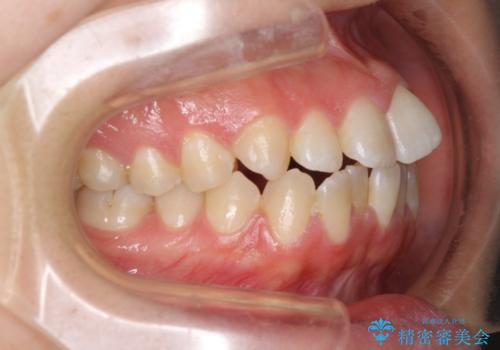

【モニター】オープンバイトをインビザラインで矯正治療

- 前歯の上下スペースによる食べにくさを気にして来院された患者様です。

インビザラインにより上下の前歯の隙間を閉じていくこととしました。

前歯のデコボコの解消と並行して上下の奥歯を圧下させるようにすることで、前歯を接触させるように計画しました。

上下の隙間に舌が入り込むことがオープンバイトの原因であったため、舌の筋肉のトレーニングも並行して行い、後戻りの抑制を図りました。